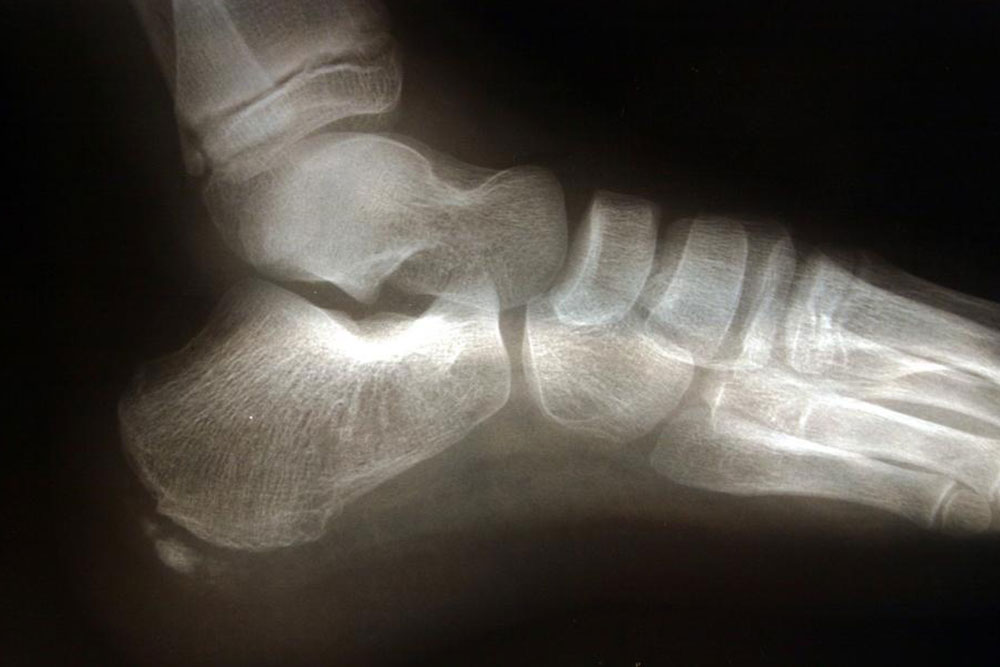

The most common foot problem is heel pain.It is felt either under the heel (plantar fasciitis) or just behind it (Achilles Tendinitis). Heel pains fluctuate from intense to moderate and often subside over time. A human foot consists of 26 bones, out of which the heel bone (Calcaneus) is the largest.

The heel supports the body weight while walking or running. It absorbs the shocks received by the body, taking all the pressure.